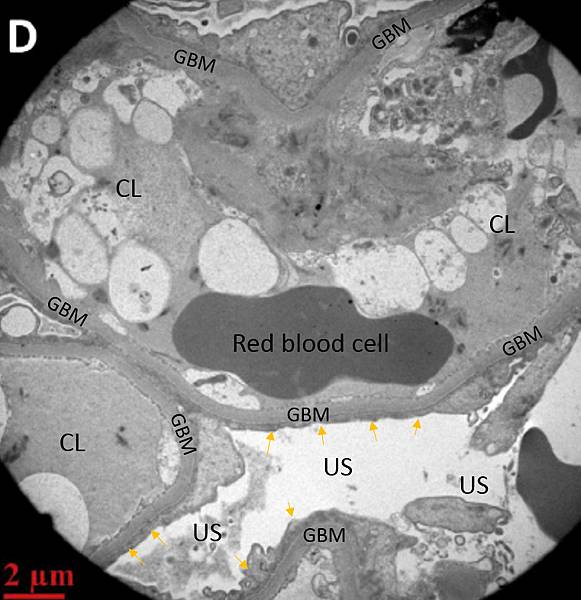

圖三:他的腎絲球電子顯微鏡顯示Podocyte的Foot process已磨平(黃箭頭),CL內充滿死亡的細胞空泡,US變寬。正常的腎絲球電子顯微鏡如下:

圖四: 正常的腎絲球電子顯微鏡圖,CL內很乾淨,US很窄。US內部GBM上的Foot process十分明顯。